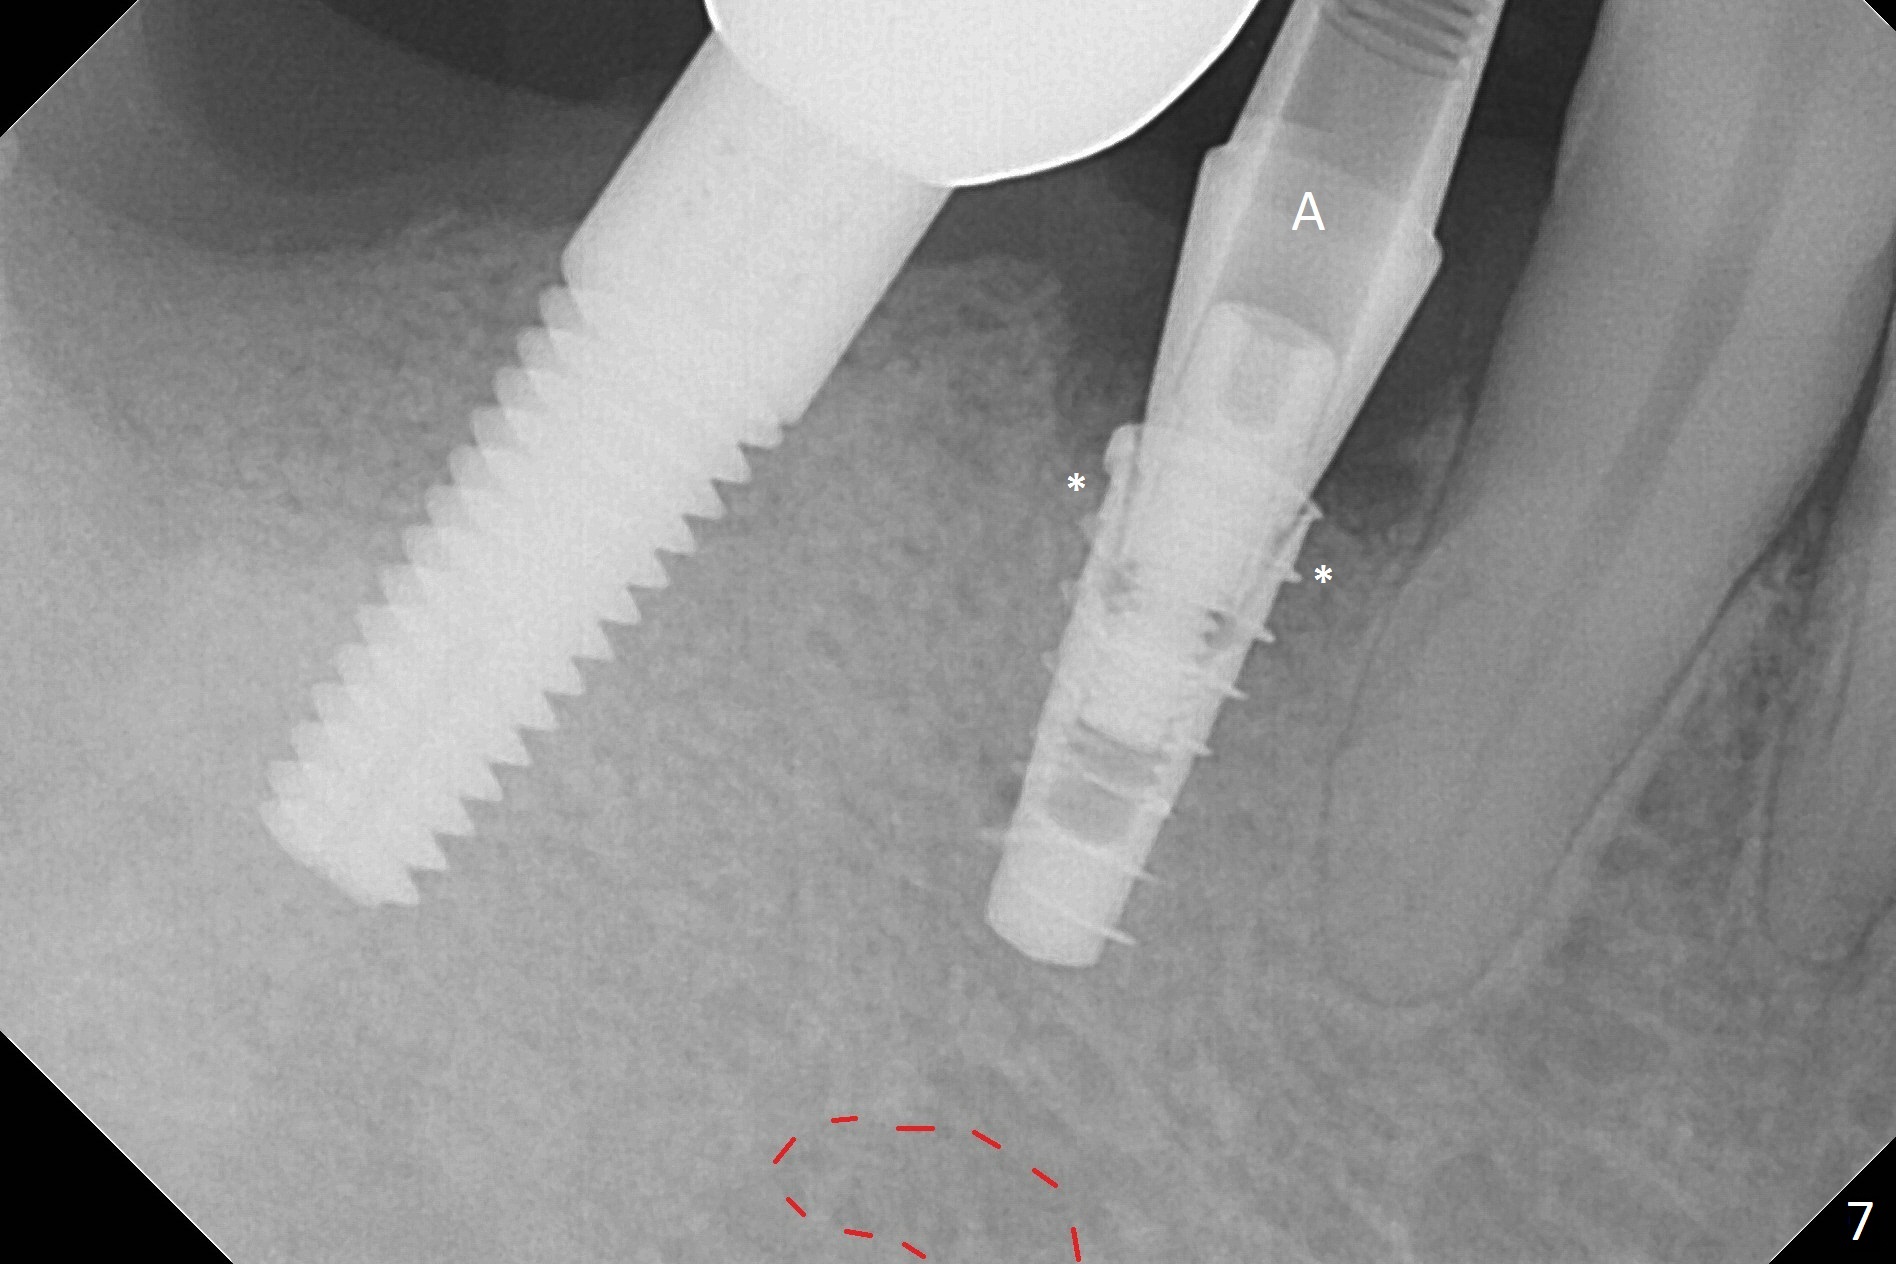

The affected tooth (#28) has buccal gingival recession (Fig.1). As expected, the buccal plate is found low after extraction. Osteotomy is established in the lingual slope of the socket with 1.5 mm drill for 13 mm (Fig.2,3). Following use of Magic Drill 3.3 mm for 13 mm, a 4x11 mm dummy implant is incompletely seated (Fig.4); it is also close to the Mental Loop (Fig.4 red line). After use of Final Drill, a 4x9 mm IBS implant is placed 4 mm and 2 mm subgingival buccal and lingual, respectively (Fig.5) with a large buccal gap (Fig.6 (40 Ncm)). After placement of allograft in the peri-implant space (Fig.7 *), a 4.5x5.7(4) mm abutment is placed (A). A piece of gauze is placed in the remaining buccal space prior to provisional fabrication (Fig.8 *). The space occupied by the gauze is later filled with collagen plug before provisional seating. The gingiva is healthy around the provisional 12 days postop (Fig.9). To reduce buccal gingival recession, the buccal margin of the provisional is shortened 4.5 months postop (Fig.10 arrow). PA taken 5.5 months postop is shown with the implant at 31. The lingual gingiva is erythematous, edematous, and recessive with +BOP and deep pockets 14 months postop (Fig.11). It appears that the small and short implant is not favorable for healing. The infected implant is removed with the missing buccal plate; bone graft is placed 15 months postop (7 months post cementation, Fig.12,13).